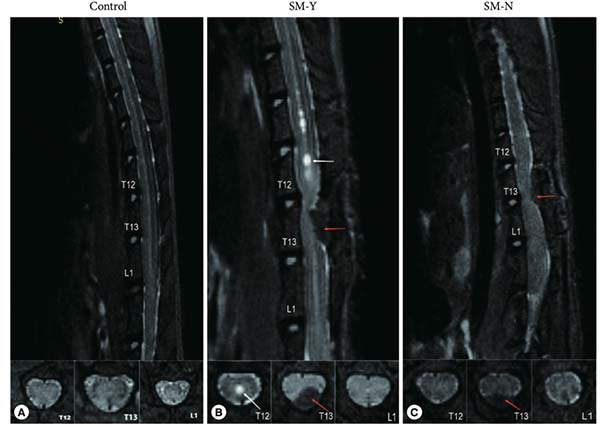

菅凤增教授团队前期通过系统总结椎管内脑脊液循环途径(图1)并进一步原创可逆性脊髓空洞大鼠模型,证实脊髓中央管梗阻可能是脊髓空洞形成的前提,而椎管内蛛网膜下腔阻塞则是疾病始动的诱因(图2)。

图2中央管闭塞可能是脊髓空洞形成的前提条件 大鼠正中矢状位和轴位核磁共振成像。(A)空白对照组。(B) 造模阳性组SM-Y组: T11-L2处串珠状脊髓空洞(白色箭头)。(C) 造模阴性组SM-N组: 无脊髓空洞形成。红色箭头表示棉条受压部位。Neurospine 2023;20(4):1-12

(蒋川、王心宇供图)